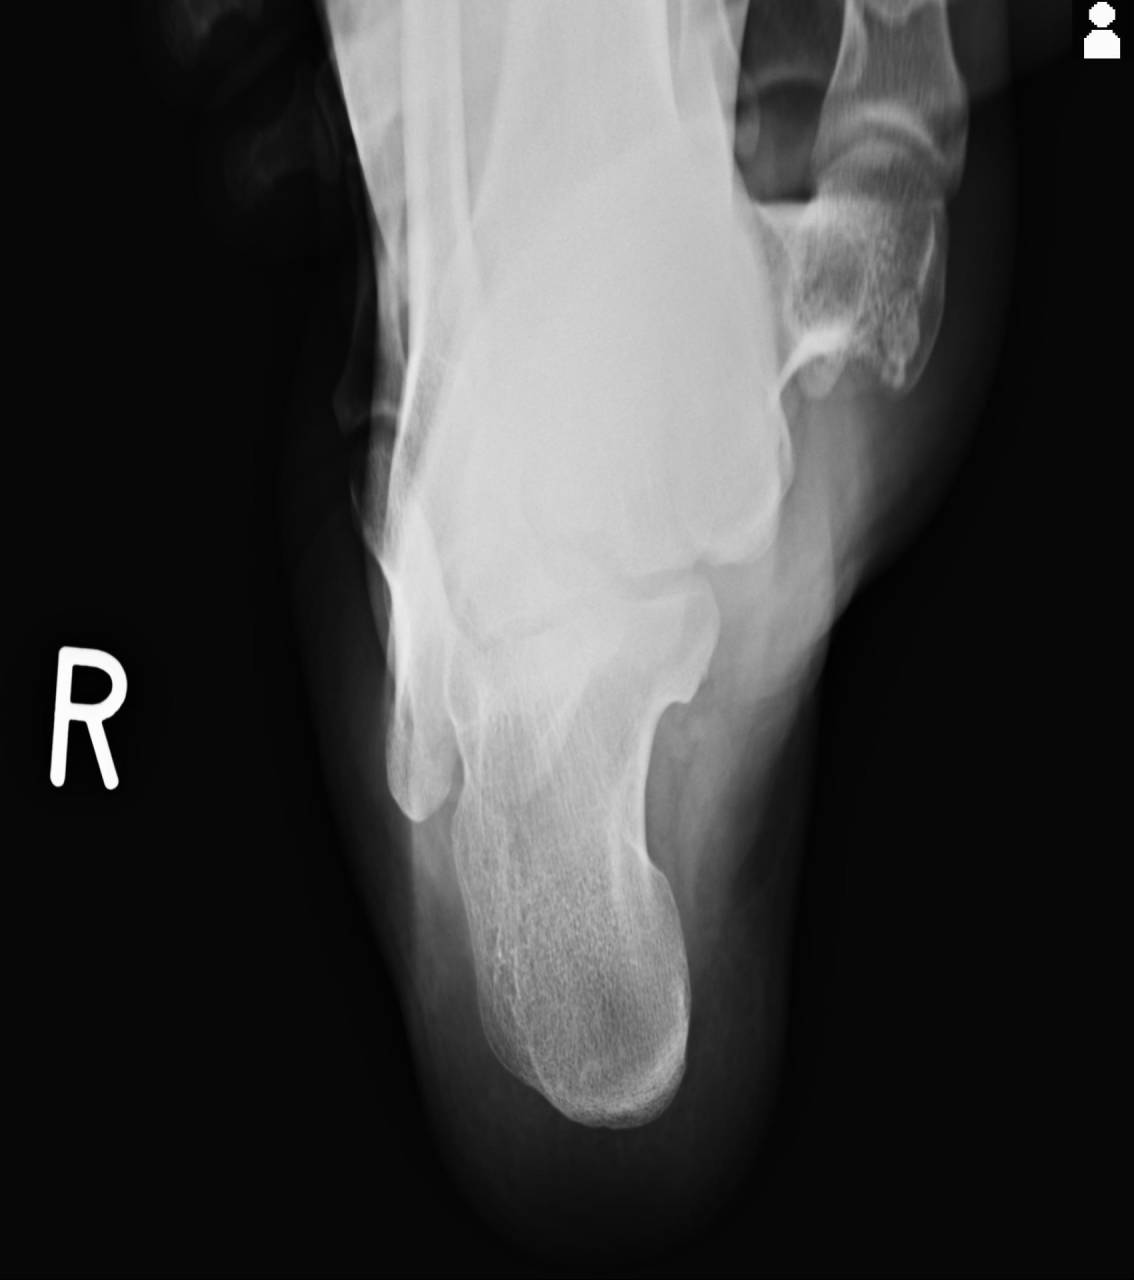

骨折の疑いがあったため当整骨院が提携している病院にてレントゲン検査を依頼し、撮影した画像を確認すると徒手検査、エコーで確認した部位に骨折線が確認できました。

レントゲン画像で見るとそこまで大した変化が無いように見えますが、エコーにて拡大された組織を細かくチェックすると健側との差が明確に分かることから骨折の判定も難しいケースだと考えます。